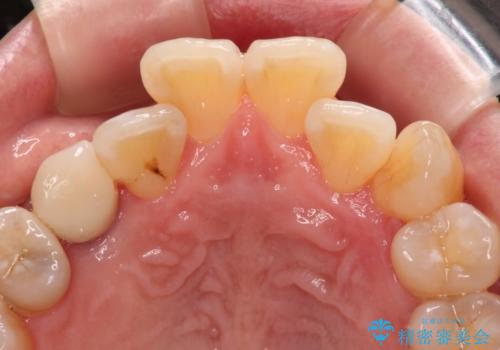

- 前歯などに、むし歯でボロボロになった歯があるとのことで来院された患者様です。

むし歯により歯冠が崩壊してから長いこと経過しているとのことで、歯を失ったことによる他の歯への影響はあまりないと判断されたため、審美領域である上顎前歯部のみにインプラント補綴治療を行うこととしました。

2本の歯が前後に重なった状態でむし歯となっていたので、抜歯後に歯肉や骨の状態が落ち着くのを待ち、インプラントを埋入することとしました。